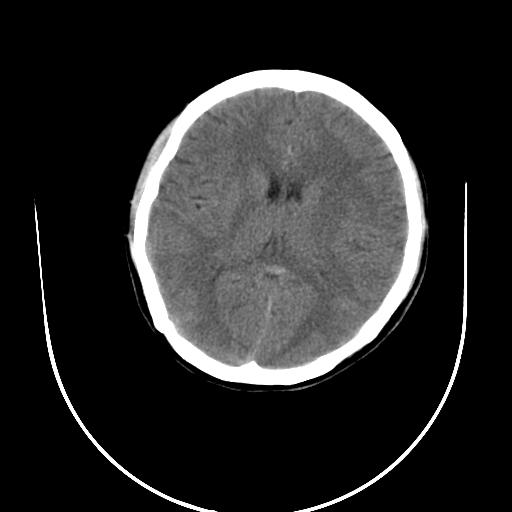

标题: CT10010:女/24岁,癫痫一周,发作时间不固定. [打印本页]

标题: CT10010:女/24岁,癫痫一周,发作时间不固定.

右侧额叶正常吗?

右额叶镰旁饱满.

右侧外侧沟?中央沟?可能有问题,不知以前有没有癫痫过,最好是增强下,排除局部血管畸形等病变

倒数第6幅图中线结构有点偏,而侧脑室额角未见异常,可结合增强扫描。